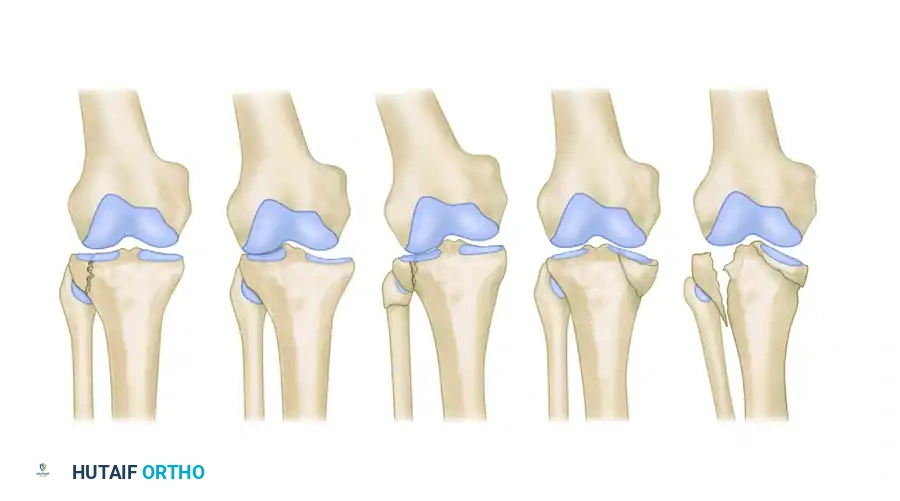

Classification of tibial plateau fractures as described by Hohl and Moore: type 1, minimally displaced; type 2, local compression; type 3, split compression; type 4, total condyle; and type 5, bicondylar.

Hohl and Moore Fracture Patterns

- Type 1 (Minimally Displaced): Fractures with less than 4 mm of depression or displacement. Often amenable to conservative management or percutaneous fixation.

- Type 2 (Local Compression): Analogous to a central depression without a peripheral split.

- Type 3 (Split Compression): Analogous to the Schatzker Type II, featuring both a cleavage plane and articular depression.

- Type 4 (Total Condyle): Involves the entire medial or lateral condyle, often with a fracture line exiting through the opposite intercondylar eminence.

- Type 5 (Bicondylar): Involves both condyles with varying degrees of comminution.